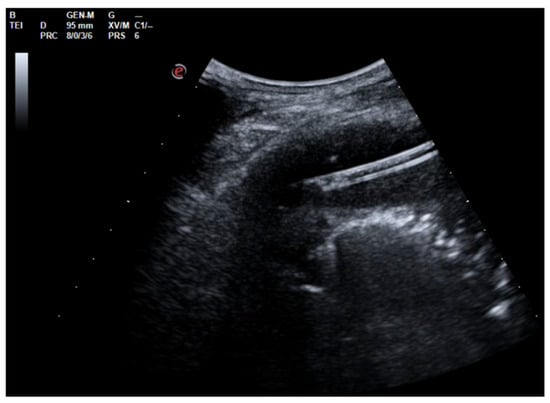

A 26-year-old man was admitted to our hospital for worsening dyspnea at rest and pain in the right hemithorax. The patient complained of a fever (39.5 °C) and productive cough for about 1 week, with mild hemoptysis in the days prior. His medical history included bilateral bronchiectasis and bronchial asthma, for which he received inhalation therapy with a long-acting antimuscarinic agent, long-acting bronchodilator, and inhaled corticosteroid. He had no family history of respiratory disease and had been tested for cystic fibrosis transmembrane regulator (CFTR) gene mutations, with negative results. The patient did not smoke cigarettes, drink alcohol, or use recreational drugs. An arterial blood gas (ABG) analysis showed acute hypoxemic normocapnic respiratory failure; therefore, oxygen therapy with a 28% FiO2 via a Venturi mask was administered. Chest radiography showed an area of opacification at the right base. Empiric antibiotic therapy with 12 mg/kg teicoplanine (Q8H) and 4.5 g piperacillin/tazobactam (Q6H) was then started on suspicion of community-acquired pneumonia. Blood tests upon his admission showed leukocytosis (WBC 18.84 × 109 cells/L) with predominant neutrophils (14.5 × 109 cells/L). Legionella and pneumococcal antigens in his urine were negative. Blood cultures after 72 h were negative. Chest ultrasonography revealed a multiloculated effusion (Figure 1).

Figure 1. Chest US at admission. Multiloculated pleural effusion.